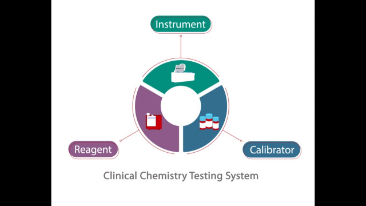

???? ??? ???

??? ??? ? ??